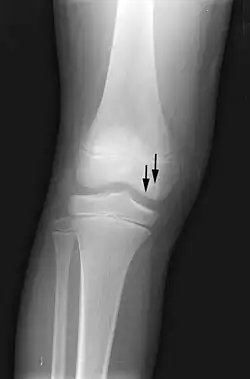

Front X-ray of right knee of an adolescent (epiphyseal plates are open): arrows point to avascular necrosis and developing osteochondritis dissecans in the outer medial condyle of femur

X-ray images of avascular necrosis in the early stages usually appear normal. In later stages it appears relatively more radio-opaque due to the nearby living bone becoming resorbed secondary to reactive hyperemia.[2] The necrotic bone itself does not show increased radiographic opacity, as dead bone cannot undergo bone resorption which is carried out by living osteoclasts.[2] Late radiographic signs also include a radiolucency area following the collapse of subchondral bone (crescent sign) and ringed regions of radiodensity resulting from saponification and calcification of marrow fat following medullary infarcts.